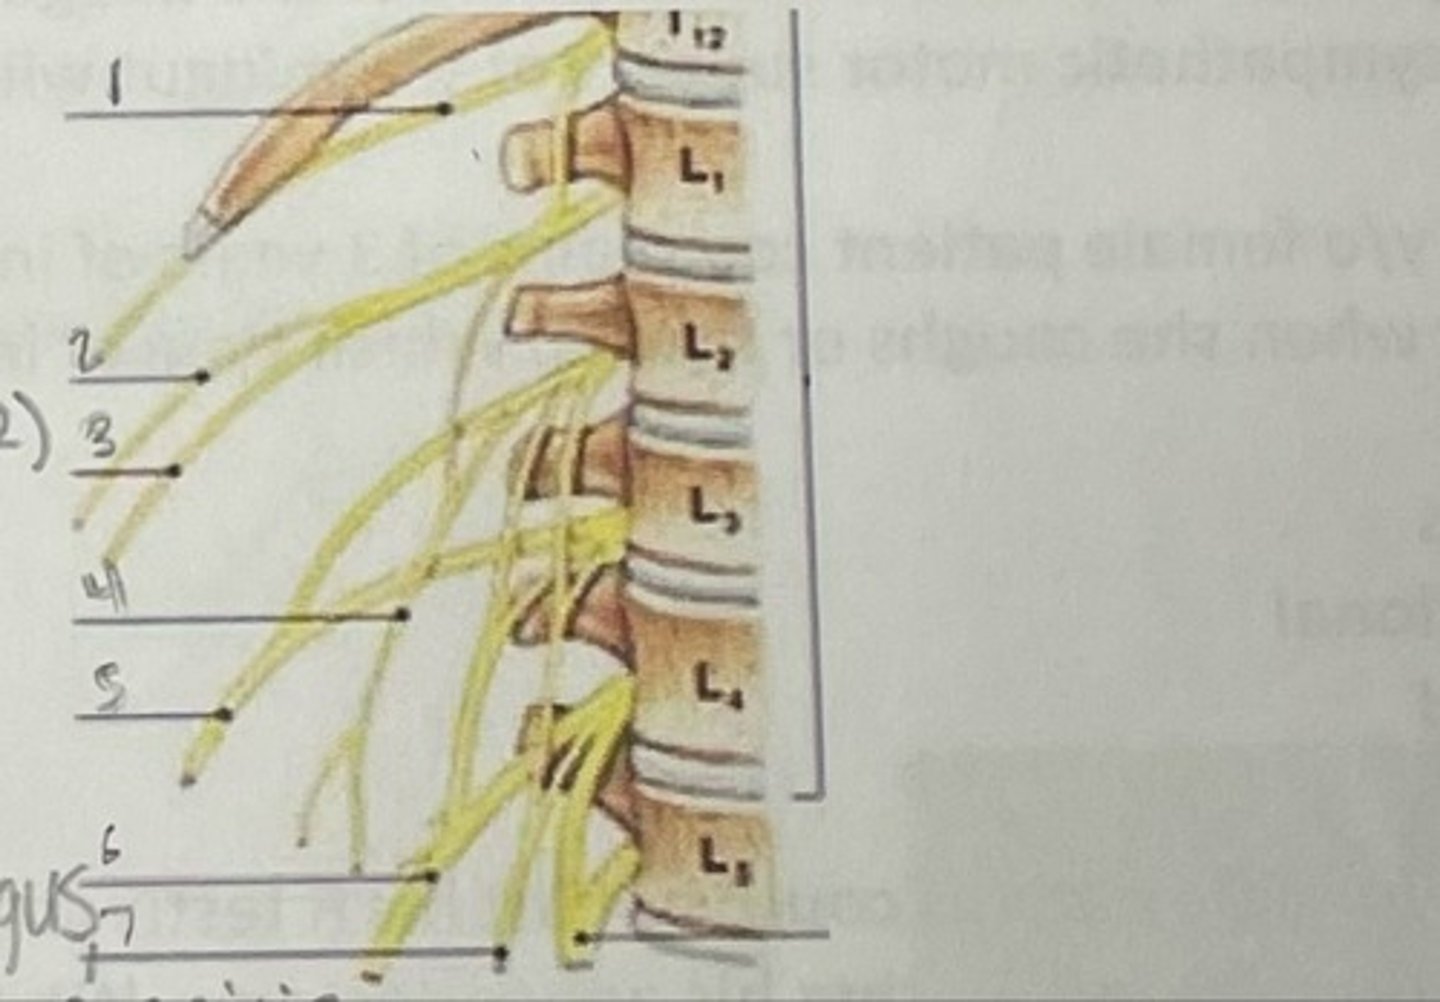

What is 1

Illiohypogastric nerve (T12/L1)

What is 2

Illioinguinal nerve (L1)

What is 3

Genitofemoral nerve (L1-L2) ; on top of psoas

What is 4

lateral femoral cutaneous nerve (L2-L3)

What is 5

Femoral Nerve (L2-L4)

What is 6

Obturator nerve (L2-L4)

What is 7

Renal artery